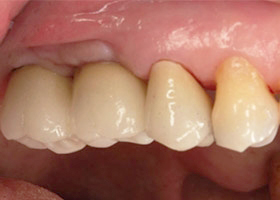

最後裝置假牙

完成照片